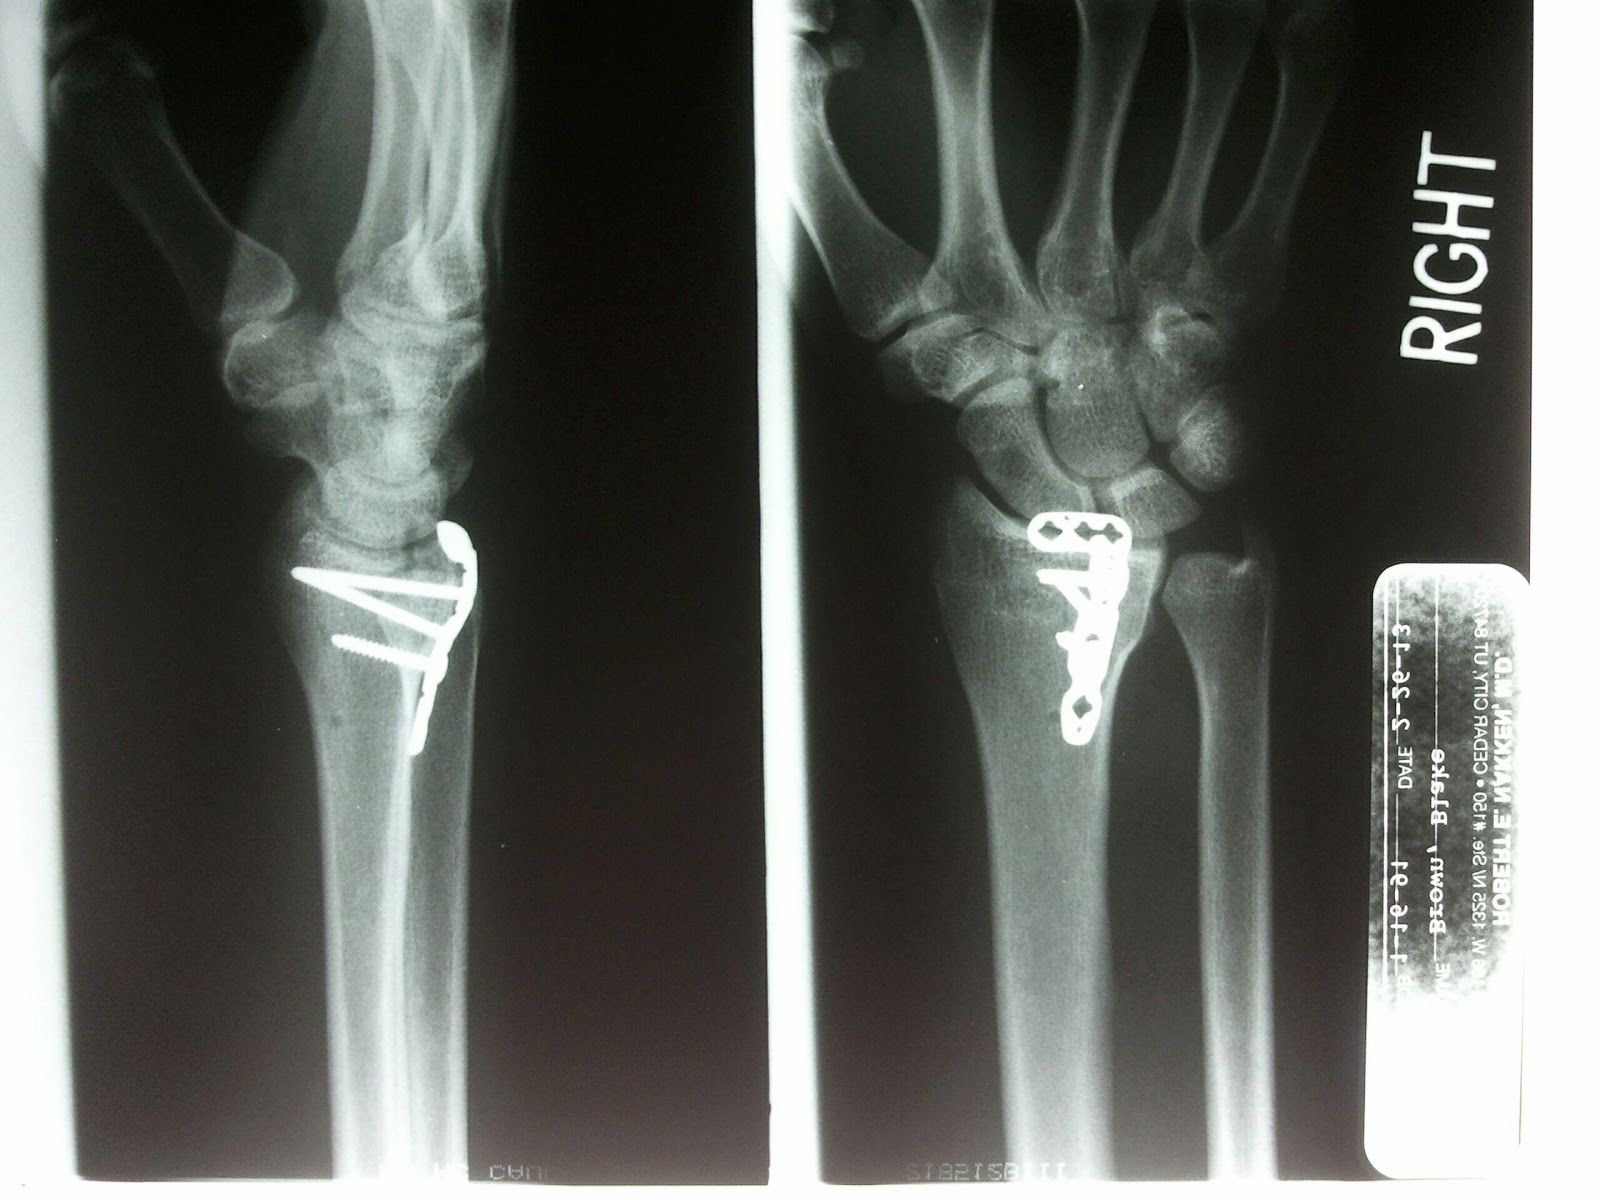

Unfortunately Valentine's got a bit overshadowed by the news that one of my brothers had fallen from the roof and shattered his wrist.  He went to the ER, and was told he needed surgery.  Funny guy.

To be perfectly honest, I'm a little bit surprised this was the first time he has ended up in the hospital for self-inflicted injuries.  I was just glad he was okay, and I think he's glad he can get back to weight lifting.  Haha.